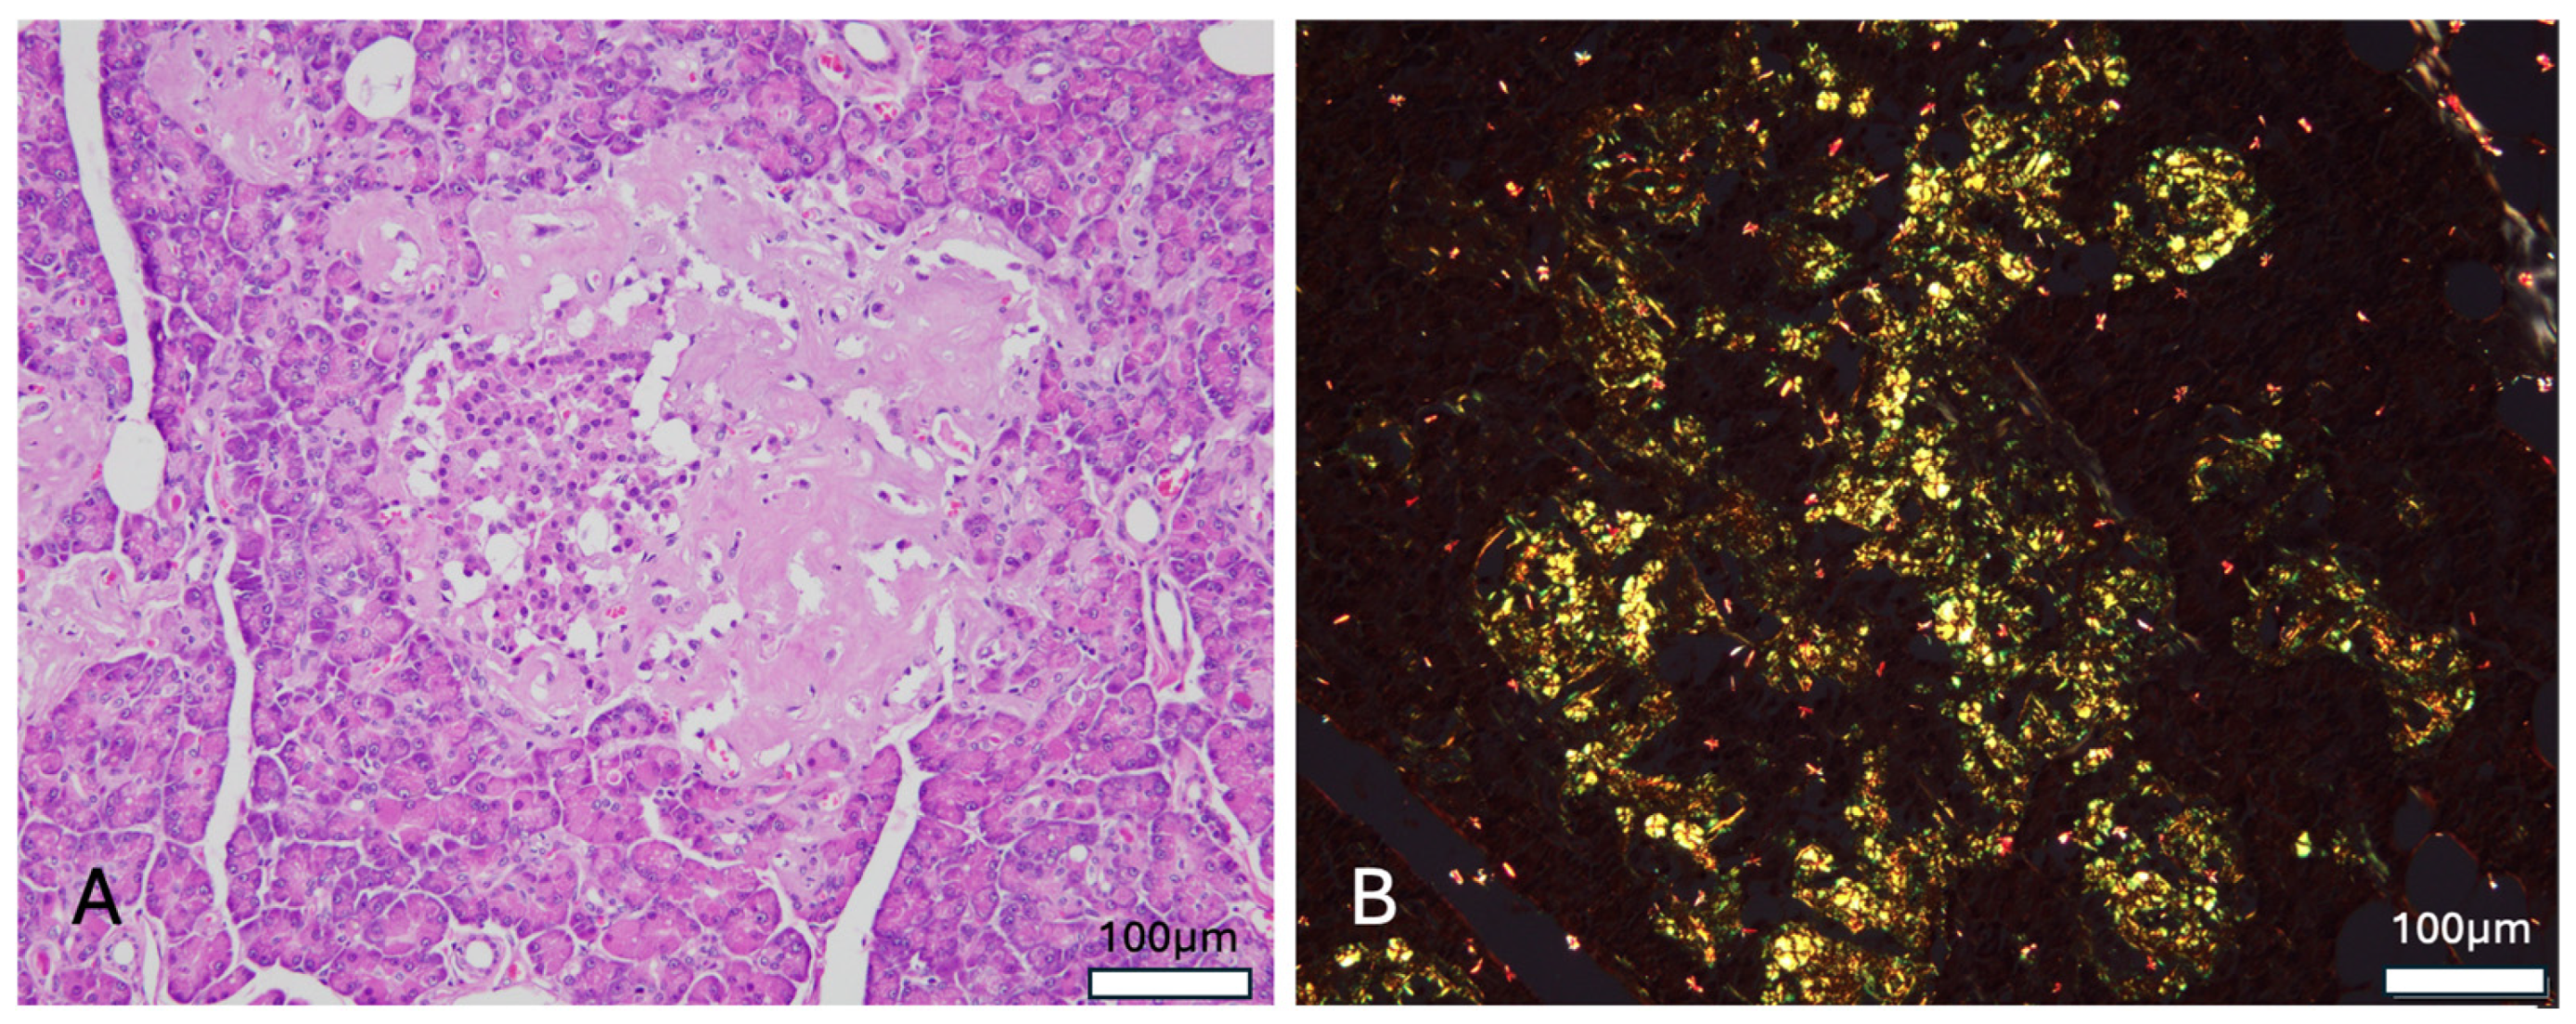

Histological examination of the pancreas revealed deposition of an amorphous eosinophilic material around pancreatic endocrine islets, with some lesions expanding into the adjacent exocrine acinar tissue (

Figure 3A). Approximately 70% of islets seen within the cut section were affected. Congo red staining demonstrated apple-green birefringence under polarized light, consistent with amyloid deposition (

Figure 3B). Immunohistochemical analysis for islet amyloid polypeptide (IAPP) was not performed due to cost and logistical limitations. In the kidney, focal thickening of the glomerular basement membrane was observed in some glomeruli, along with mild to moderate focal adhesion at the glomerulo-tubular junction, where collagen deposition was confirmed via Masson’s trichrome stain. Additionally, the adrenal parenchyma was found to contain two small osteolipomas composed of mature adipose tissue and bone elements. In the skeletal muscle, 2 small foci of Sarcocystis infection were identified within the myocytes, each containing numerous large bradyzoites.

Primary findings on postmortem, particularly the presence of pancreatic islet amyloidosis were most consistent with that of T2D as observed in humans, and other species such as the cat [

7,

10]. Islet amyloid polypeptides (IAPP), a neuroendocrine hormone involved in the regulation of glucose homeostasis, is normally co-produced with insulin in response to glucose [

10]. IAPP sequences are susceptible to sudden post-translational modifications that increase the risk of misfolding and thus amyloid formation only in certain species, including humans, cats and non-human primates [

10]. In cases of T2D, the resulting amyloidosis within the Islets of Langerhans of the pancreas further leads to β -cell dysfunction and cytotoxicity, a hallmark feature of this form of the disease [

10]. Although pancreatic amyloidosis has not yet been documented in the binturong, our findings in conjunction with the classification of Viverridae within the suborder Feliformia suggest that the feline model of T2D may be a useful tool in understanding the progression of diabetes in the species.

Several limitations to this paper include the single-case nature of this report. Further observations and studies regarding similar presentations within the species will strengthen our understanding of the presentation and pathogenesis of this disease process in binturongs. Furthermore, the lack of immunohistochemical analysis to confirm the nature of the amyloid deposits seen is noteworthy. While the presence of amyloid deposition in this case can be confirmed by histology and Congo Red staining, the use of immunohistochemistry could further strengthen this report by differentiating IAPP from other amyloid types such as serum amyloid A, or amyloid light-chain. As this test has not yet been validated in the species, an assay with cross-reactivity to the domestic cat would likely serve as the best available proxy. Nevertheless, the morphological features and restriction of deposition to the pancreatic islets in this patient are most consistent with IAPP deposition, as reported in cats and humans.